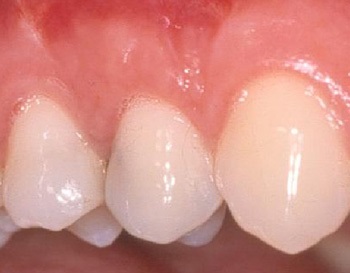

Κάλυψη της υποχώρησης ούλου με μόσχευμα ούλου

Κάλυψη της υποχώρησης ούλου που οφείλεται σε τραυματικό βούρτσισμα